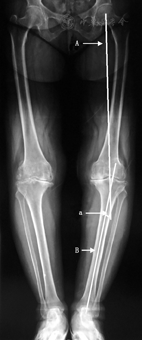

其中,手术时间定义为从切开皮肤至皮肤缝合完毕的时间,由巡回护士记录,精确至分钟。冠状面机械轴力线的测量方式是冠状面髋-膝-踝(HKA)角(图1),即下肢全长正位X线片上髋关节中心至膝关节中心的连线,和膝关节中心至踝关节中心连线的夹角,由非术者团队的一位骨科医师进行测量。HKA角的目标角度定义为0°,膝关节内翻时角度为正,膝关节外翻时角度为负,±3°为可接受区间,超出此区间定义为力线偏移。

术后有11例患者下肢冠状面机械轴力线呈膝外翻,平均外翻2.0°(0.3°~2.9°),其余85例患者呈膝内翻,平均内翻2.4°(0.1°~8.1°)。以术后HKA角±3°作为可接受区间,力线良好患者74例(77.1%),力线偏移患者22例(22.9%),其中CAS-TKA组患者术后力线偏移比例最低(11.8%),对照组最高(30.3%),PSI-TKA组居中(27.6%),3组差异无统计学意义(χ2=3.771,P=0.151)。